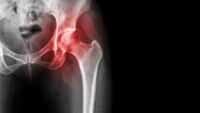

Because hip pain has many complex causes, it’s essential to get the right diagnosis to treat your acute or chronic hip pain appropriately and effectively. Some of the more common causes of persistent hip pain are reviewed below.

Osteoarthritis and rheumatoid arthritis are the most common causes of chronic hip pain, often resulting from age-related wear and tear on the hip joint. Arthritis pain is usually felt in the front of the hip or the groin area.